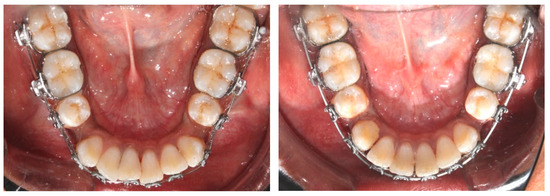

2.3.1. Piezocision Procedure (PZ)

2.3.2. Micro-Osteoperforation Procedure (MOP)